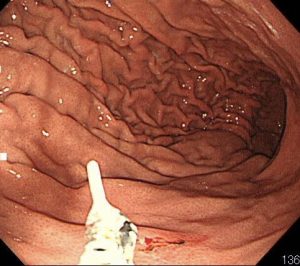

除去後の粘膜です。粘膜が腫れ上がっており、炎症を起こしていたことが分かります。

2匹目です。胃体上部(胃の入り口付近)に食いついています。

同様に鉗子で除去します。